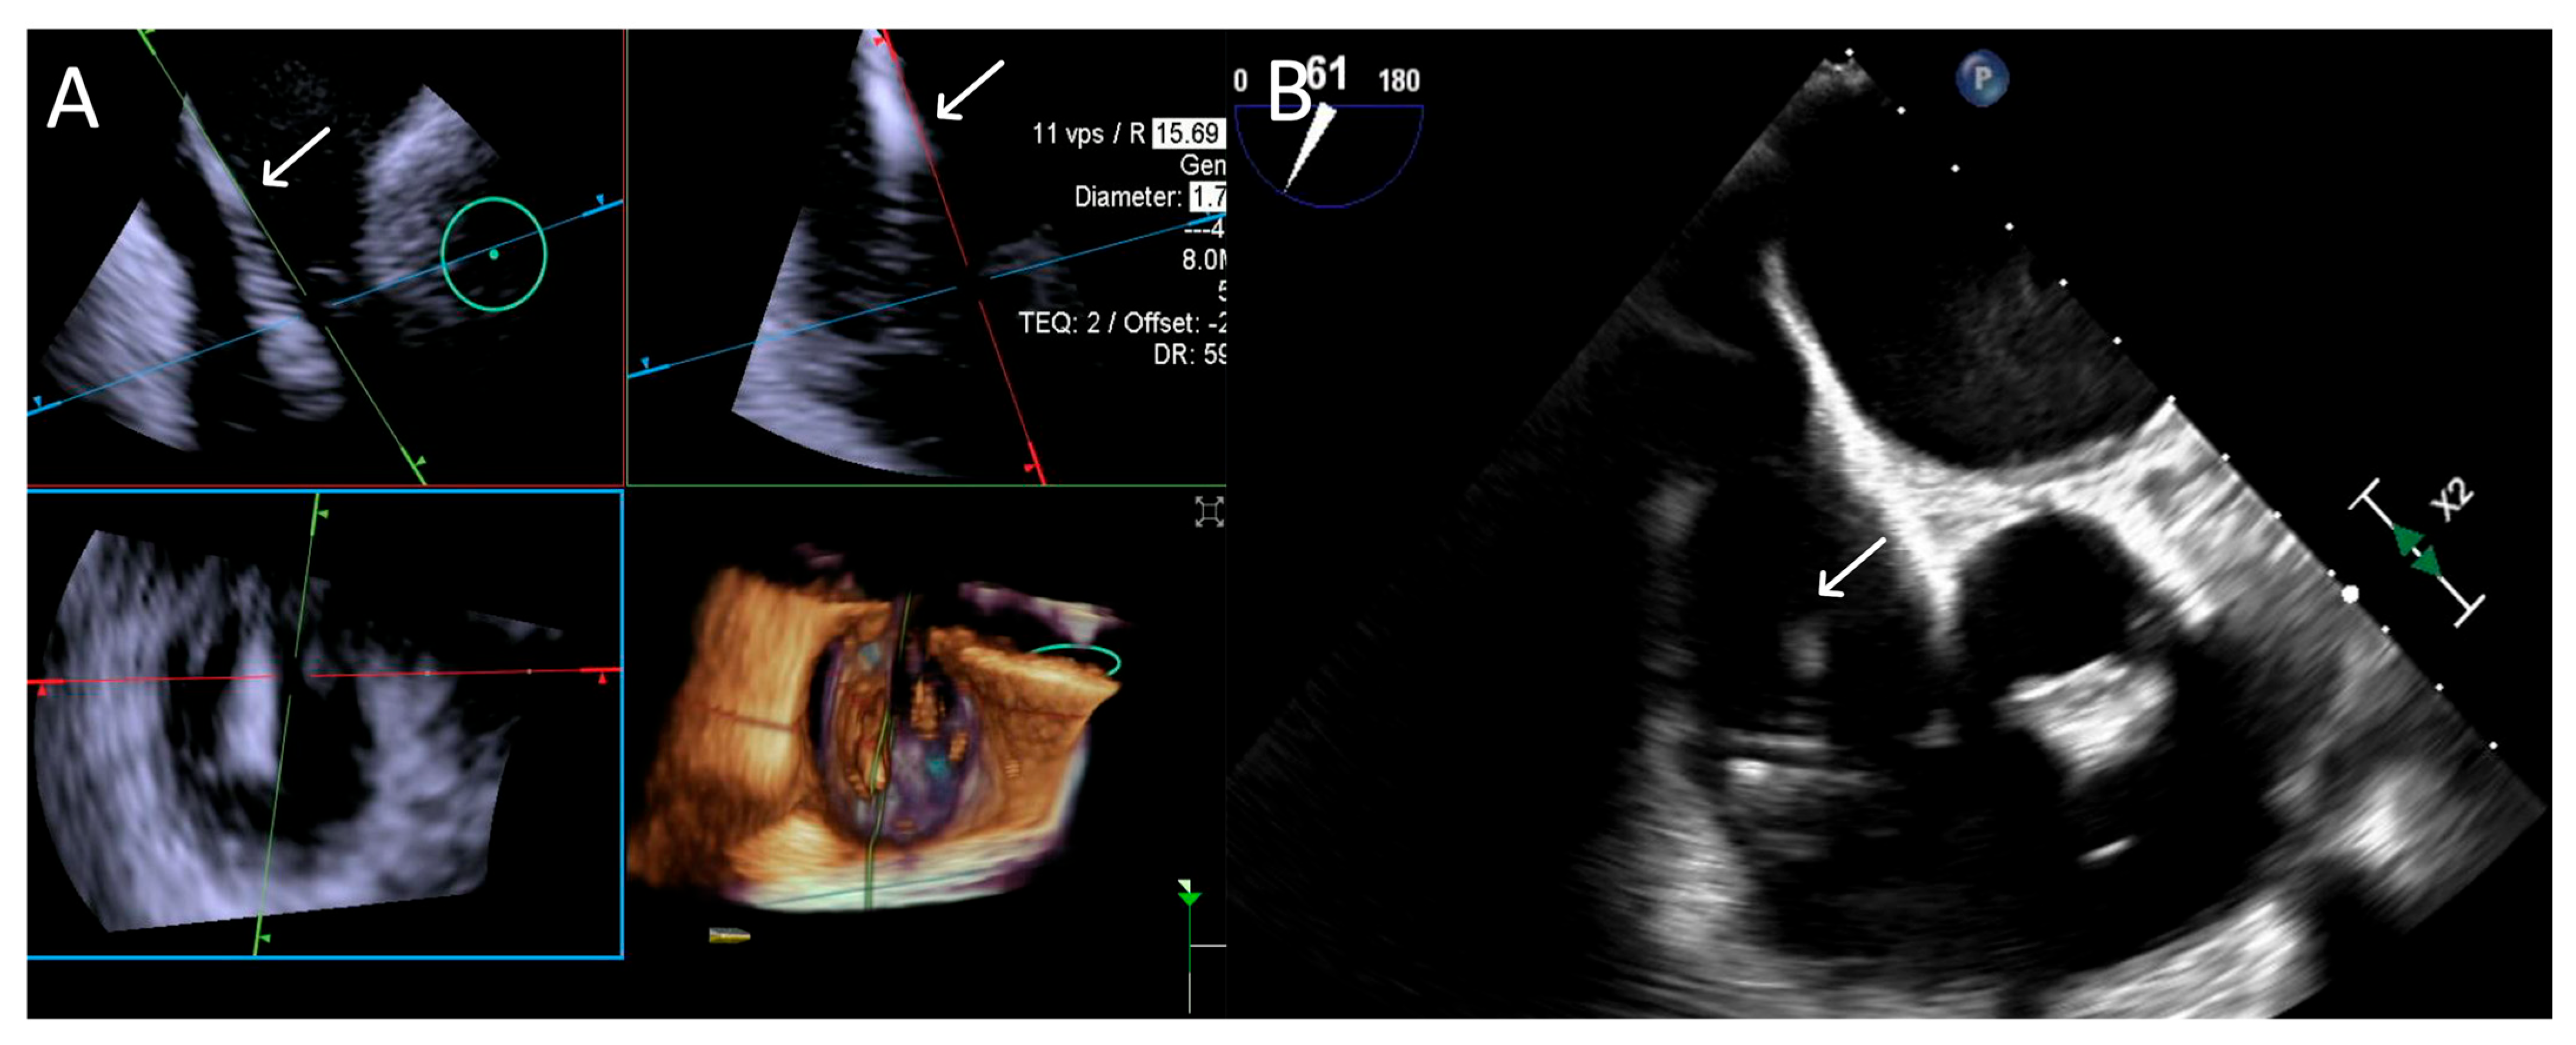

- Step number 4: ensuring perpendicularity and correct trajectory.

3.3.1. Step-by-Step Evaluation